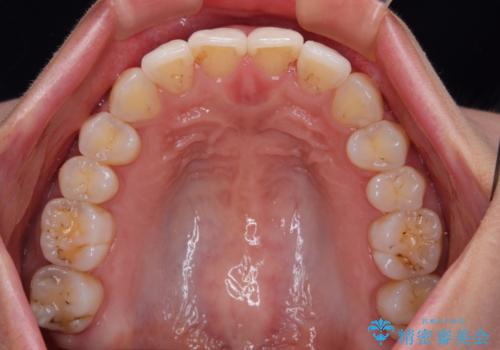

- 捻れた前歯が飛び出しており、口が閉じにくいとのことで来院された患者様です。

出っ歯というわけではないものの、前歯の捻転により口唇が押し出されている状態でした。

親知らずを抜去し、歯列全体を後方に移動させつつ、IPR(歯と歯の間を削る)でスペースを獲得し、インビザラインを用いて叢生を解消しながら前歯の突出を改善することとしました。

骨格的に上下正中がずれていたため、奥歯がしっかりと噛み合うか心配でしたが、ずれているなりに、しっかりとした咬み合わせとなりました。